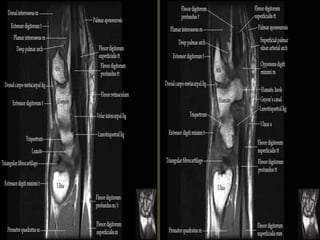

Wrist X-ray Anatomy.

Pronator quadratus.